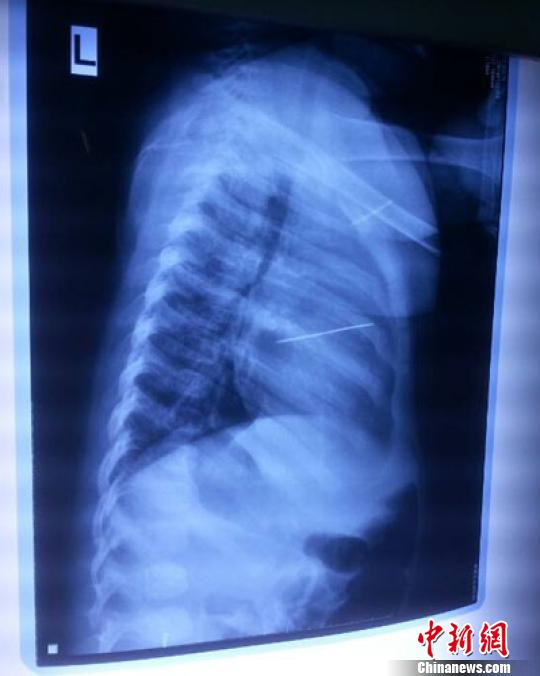

女嬰胸片提示心臟里面扎了一個縫衣針 蔡迅翔 攝

醫院胸心外科主任翟波介紹說,1月22日,小患者彤彤因為發燒抽搐來醫院就診,常規檢查時發現孩子心臟里面扎了一個縫衣針。

“第二天上午,我們做了個緊急彩超檢查,發現針是從患者右心室表面刺入,穿破室間隔,到達左心房,中間還有一部分損害到二尖瓣。于23號下午,我們就做了一個緊急手術,手術中發現,這枚針已經刺入心臟,沒入了右心室的下面,表面已經看不到針了,僅能看到一個小針眼,還在往外滲血,一點一點的滲,心包腔里面大概有100多毫升的出血,心包上一個洞,針在右心室表面刺入以后,穿過室間隔,在二尖瓣的上方,進入了左心房,在針的四周,有很多纖維沉積物,包繞著這枚針。”翟波說,他們把針取出來以后,測量了一下,長度大概是五厘米,同時發現這個針給患者左心房的后壁造成了一定的損傷,左心房的后壁已經損傷了三分之二,還剩下有左心房的外膜,很薄的一層,如果這一層再破的話,這個孩子將會引起大出血,很快就會死亡。